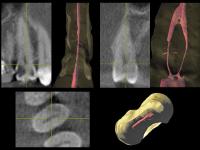

3. Анализ томограммы

- • Горизонтальный срез на границе апикальной трети (рис. 64-66): обнаруживается щелевидная форма и объединение корневых каналов 1.5 зуба в один.

- • Горизонтальный срез в 2 миллиметрах от апекса (рис. 67-68): корневые каналы опять раздваиваются.

| Рис. 64-66 Профильные срезы и 3-D визуализация апикальной трети 1.5 зуба: корневые каналы сливаются |

| Рис. 67-68 Профильные срезы и 3-D визуализация в 2 мм от апекса: корневые каналы расходятся |